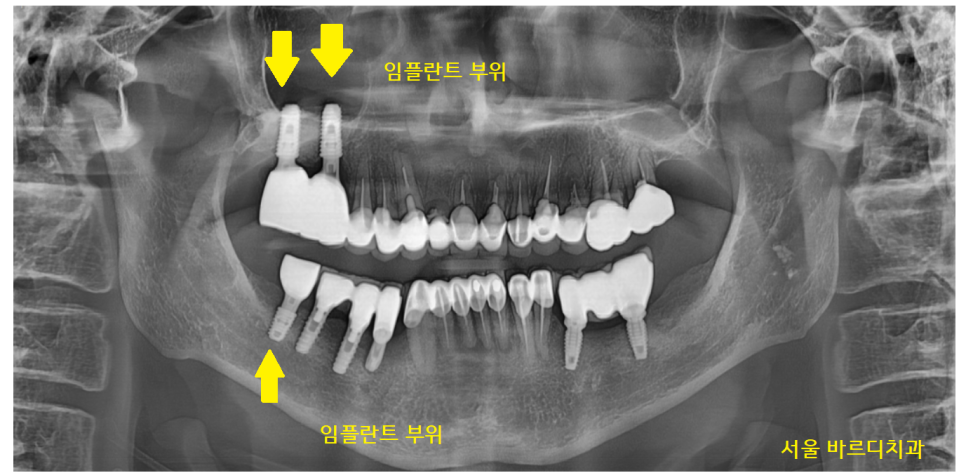

24.05.03

완성까지는 4개월 정도 걸렸는데요.

잇몸과 임플란트가 붙을 때까지

기다렸다가 머리를 만들어드렸습니다.